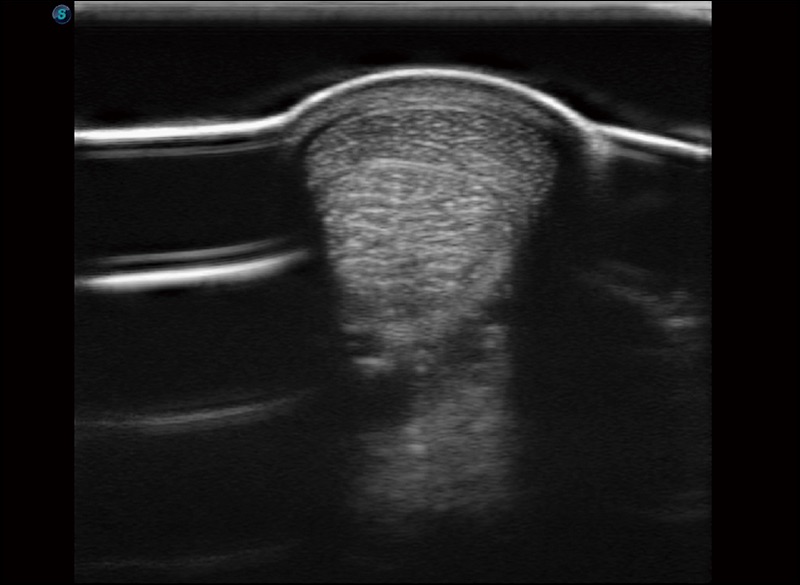

穿刺针增强

高清显示穿刺进针情况

连续波多普勒成像CW

为心脏功能评估提供更多诊断信息